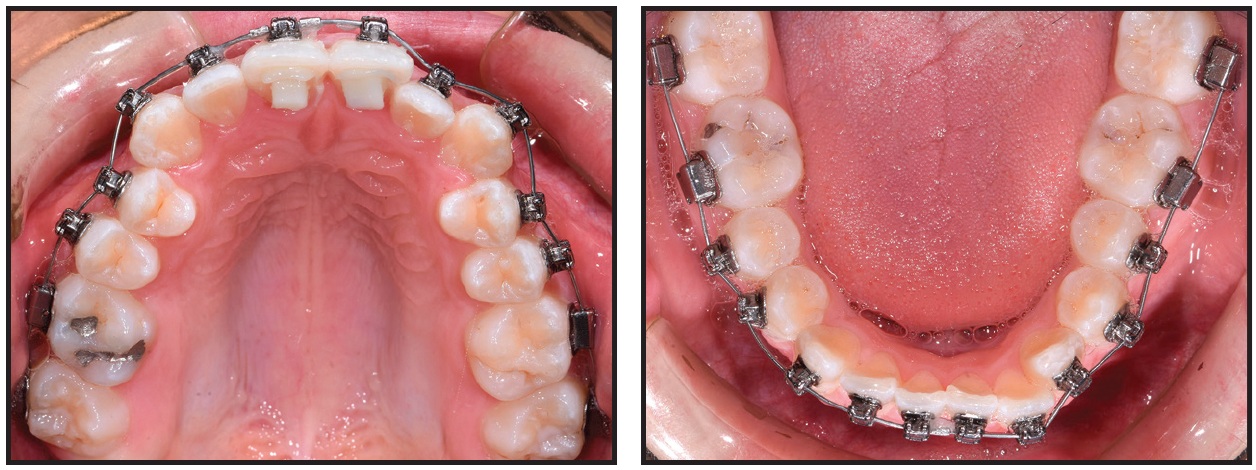

Fig. 5 Case 1. Damon Q** brackets bonded and .016" SmartArch Copper NiTi wires placed in both arches.

Fig. 6 Case 1. After five weeks of treatment, .018" × .025" SmartArch Copper NiTi wires placed in both arches.

Damon Q** brackets were bonded to all teeth in both arches: low-torque brackets on the upper and lower incisors, high-torque brackets on the lower canines, and standard brackets on all other teeth (Fig. 5). Anterior bite turbos were bonded to the lingual aspects of the upper central incisors. SmartArch .016" Copper NiTi archwires were inserted in all brackets, with no elastics worn at the start.

After five weeks of treatment, the upper right second molar was rebonded, and maxillary and mandibular archwires were changed to .018" × .025" SmartArch Copper NiTi (Fig. 6). The turbos remained in place.